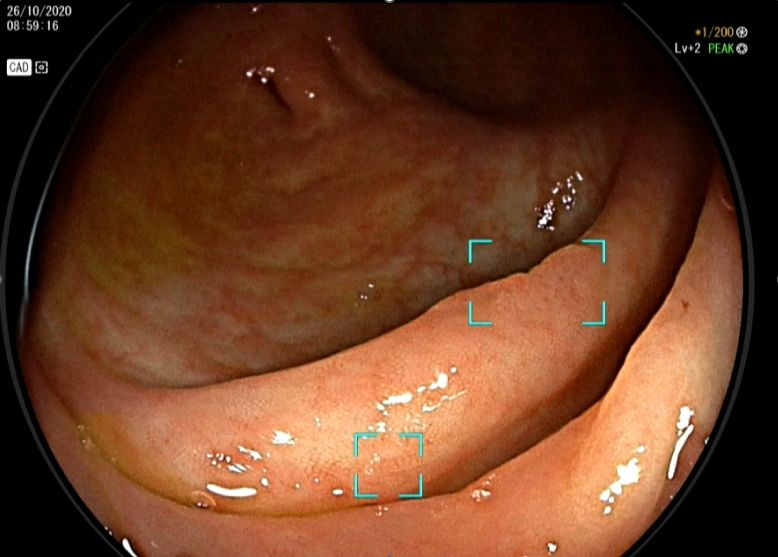

An example of DeepGI endoscopy, enhanced with AI technology, which assists physicians in detecting and alerting them to malignant polyps

At the MedPark Hospital Gastrointestinal and Liver Center, we employ the DeepGI AI tool to assist doctors in detecting, analyzing, and providing real-time alerts when malignant polyps are present during a colonoscopy. This AI-powered technology boasts an accuracy rate of up to 90%, making it an effective tool for screening early colorectal cancer.